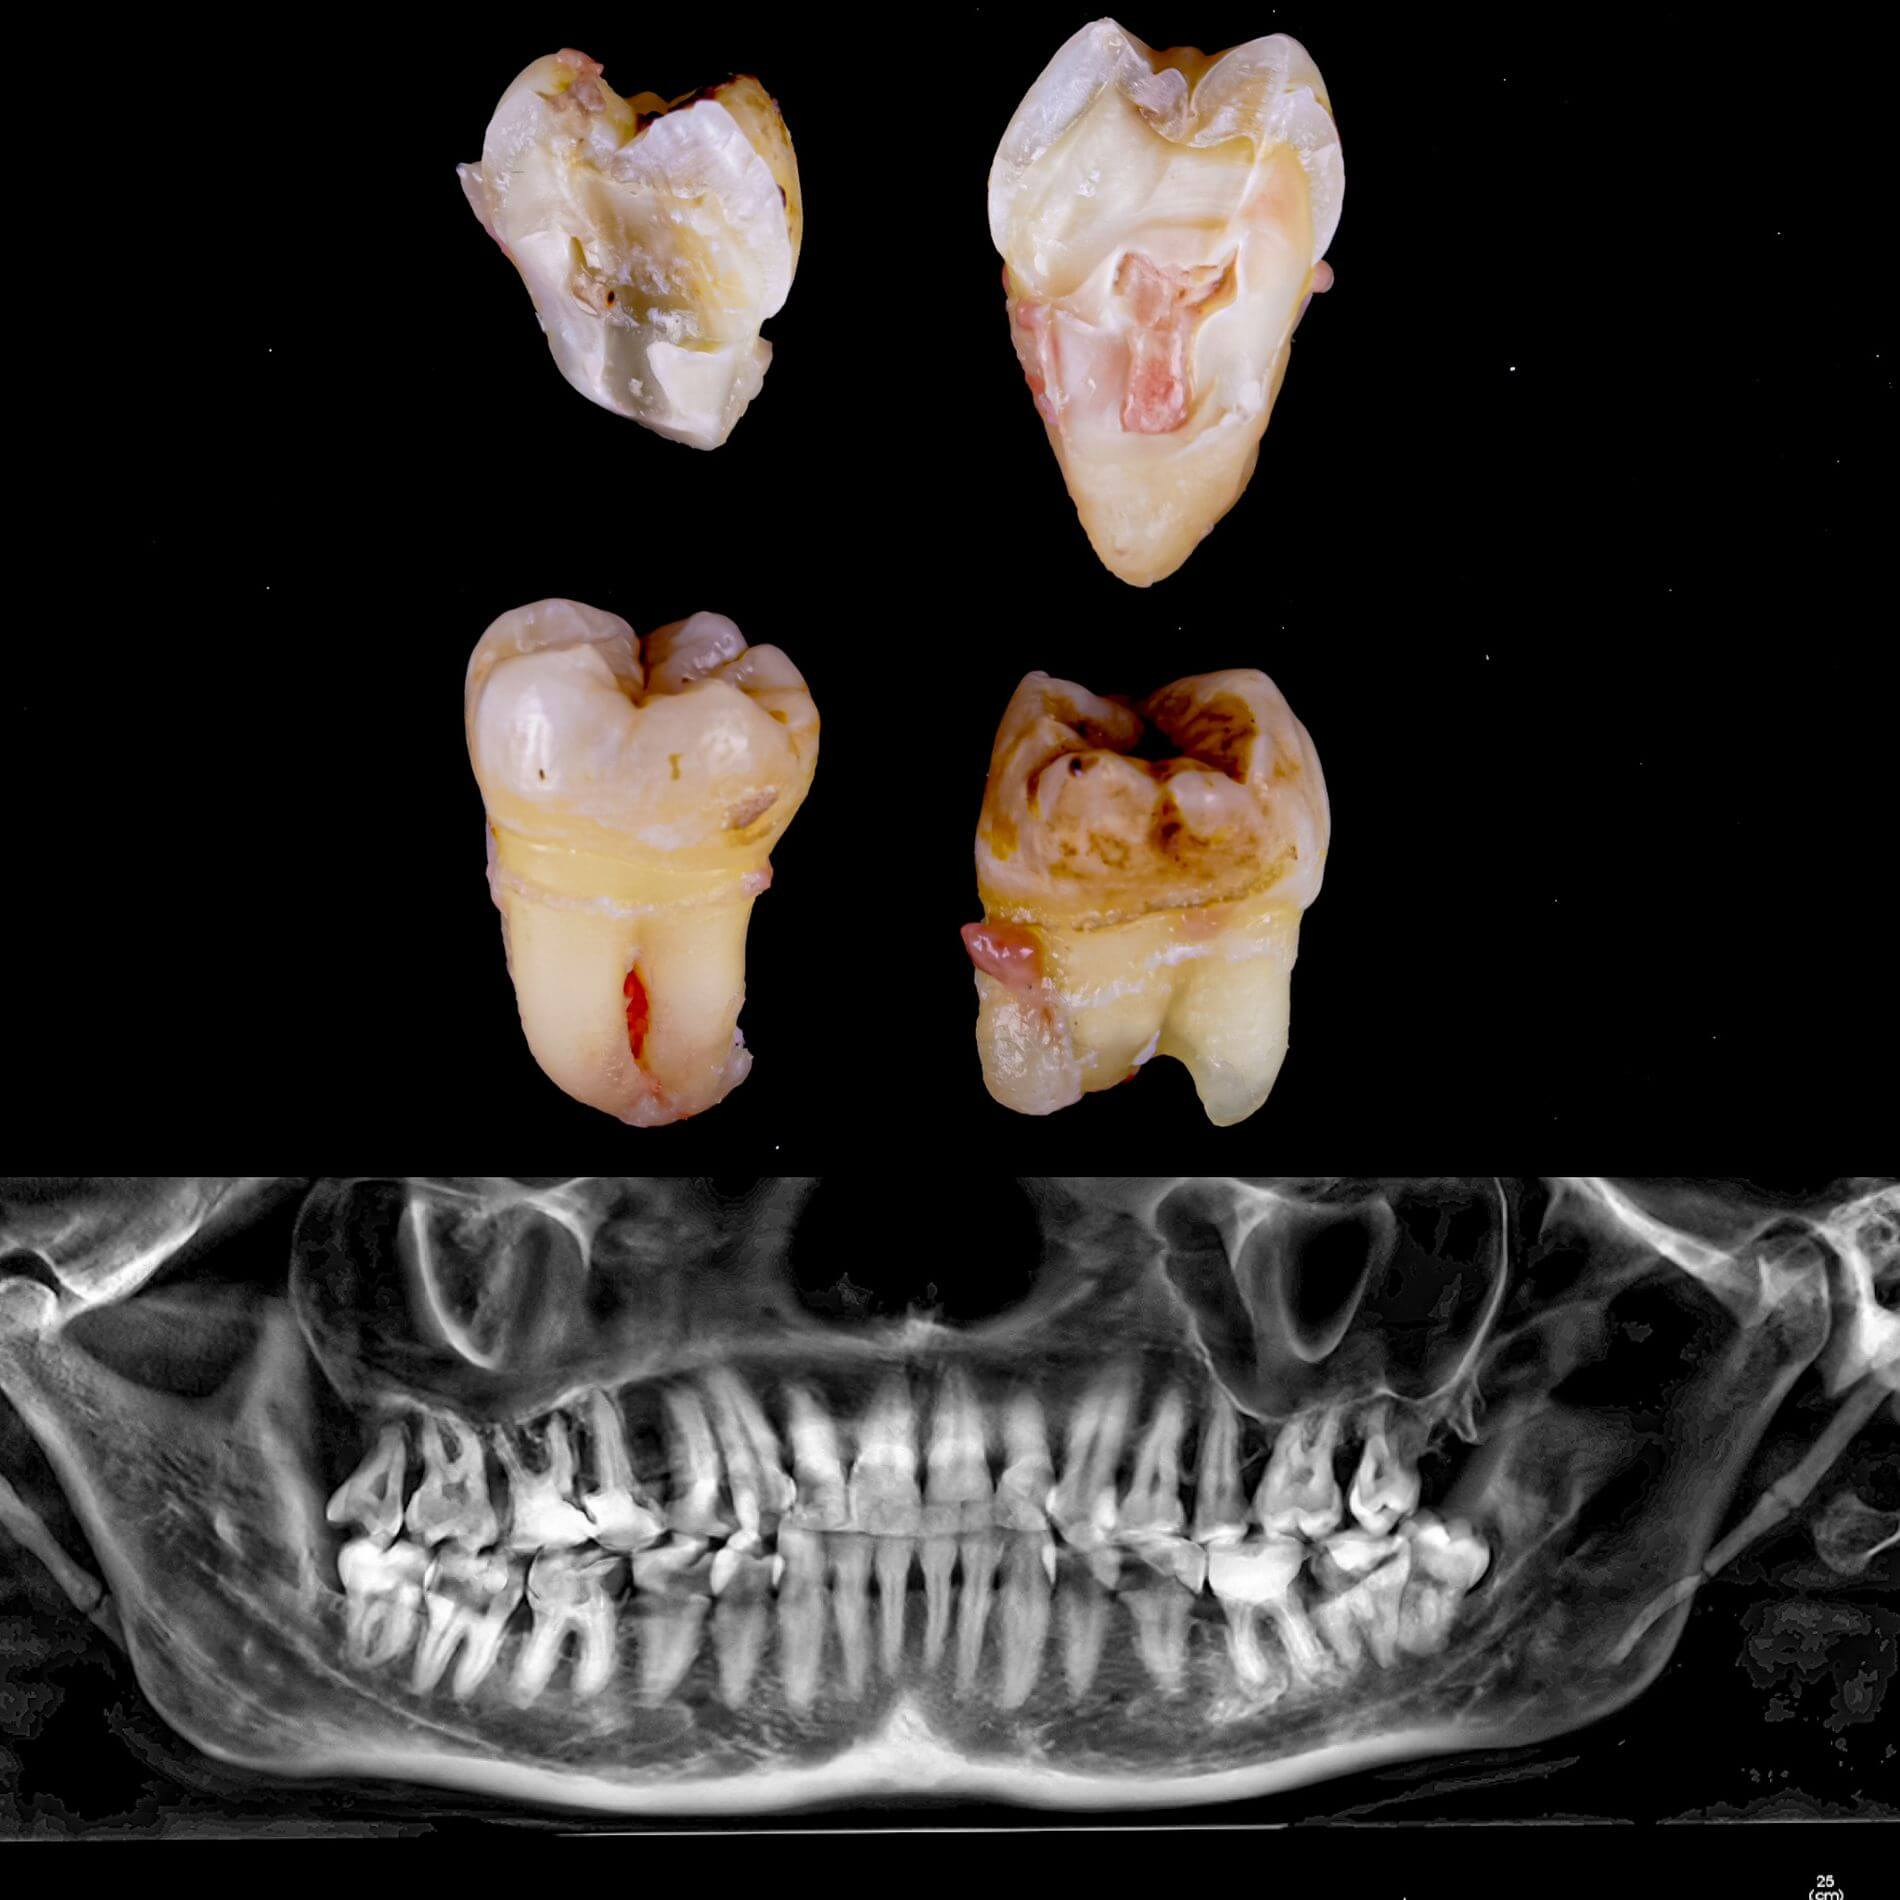

Види видалення зубів мудрості

- Повне видалення зуба - якщо зуб повністю прорізався та має зрощені корені.

- Окреме видалення коронки зуба та його коренів - якщо зуб прорізаний і корені ростуть по окремо.

- Видалення зуба за схемою 1 або 2 із розрізом ясна - якщо зуб прорізаний частково.

- Розріз ясна, звільнення зуба від прилеглої кістки ультразвуком та видалення за схемою 1 або 2 - якщо зуб не прорізався, але турбує.

Видаляти зуб мудрості рекомендується тоді, коли він давить на зубний ряд та посуває інші зуби, завдає болю або сам вже пошкоджений карієсом.

Вирвати зуб мудрості у Львові можна простіше, ніж тобі здається, в Космічній стоматології Драганчука. Почни цей шлях з простого кроку - первинної зустрічі з хірургом-стоматологом. На консультації ми зробимо основне – скеруємо тебе на 3D комп’ютерну томографію, щоб врахувати близькість нижньощелепного нерва (нижні 8-ки) та верхньощелепної пазухи (верхні 8-ки) та складемо план видалення зубів.